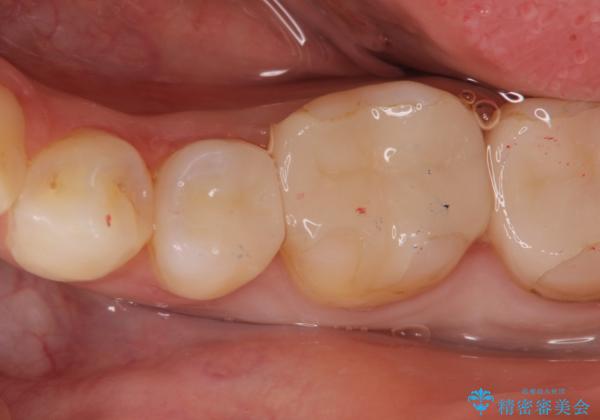

虫歯の治療(セラミックインレー)

- 定期検診にて虫歯が見つかり、セラミックインレーに治療を行っております。

e-max プレスインレーにて修復治療を行っているため適合性及び審美性の高い治療を行うことができます